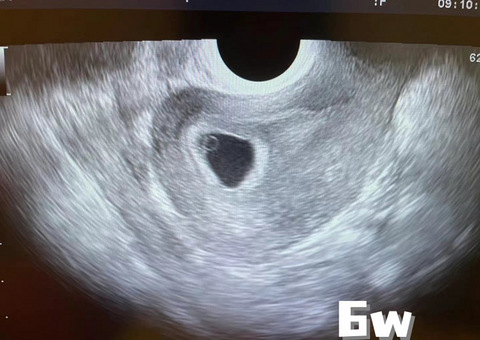

生命真是神奇,肚子里的小人就这么长大了

生命真是神奇,肚子里的小人就这么长大了 6周的时候,只是一个点点